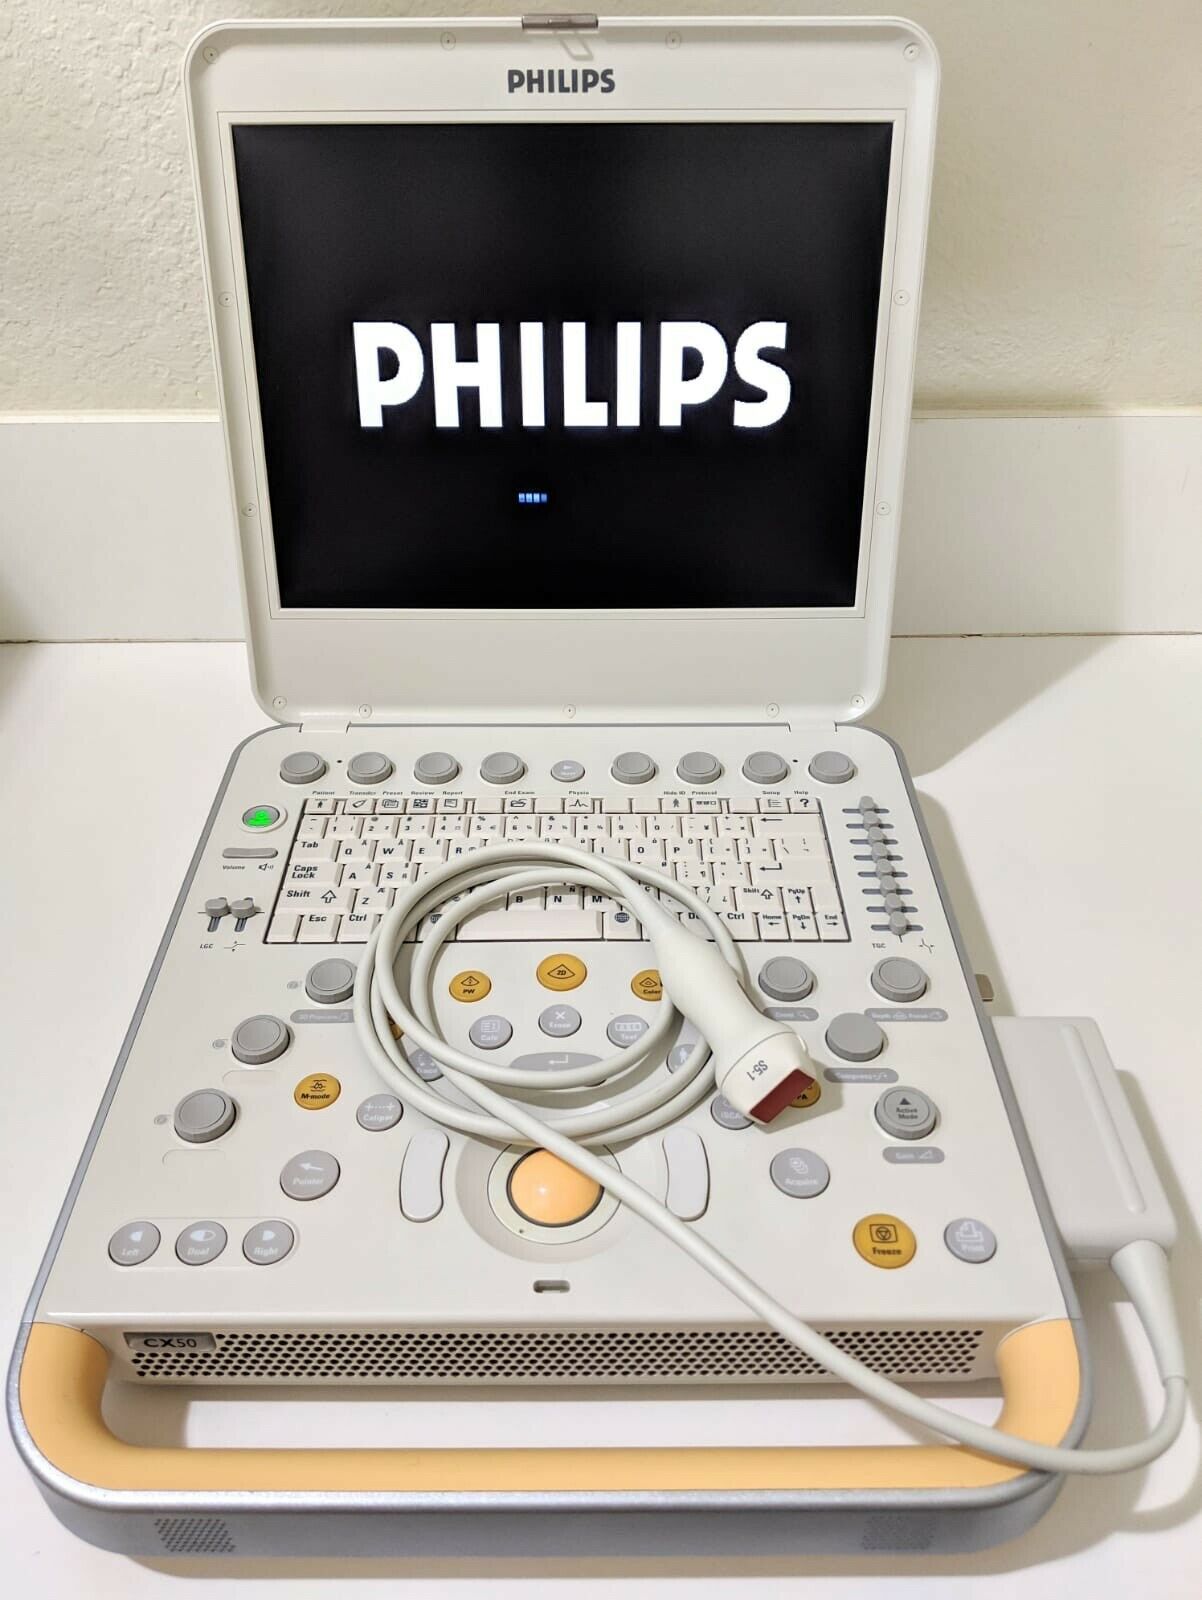

PHILIPS CX50 2013 REV 4 W/ 3 PROBES PORTABLE ULTRASOUND

The Philips CX50 2013 Rev 4 Portable Ultrasound System with three probes is a high-performance imaging solution designed for flexibility across a range of clinical applications. This compact, portable ultrasound machine delivers premium imaging quality, making it ideal for point-of-care, cardiology, vascular, and emergency medicine. Equipped with Philips’ advanced imaging technologies like PureWave crystal technology, the CX50 provides exceptional resolution and detail, even in difficult-to-image patients.

The three included probes offer versatility, allowing clinicians to perform various exams, from cardiac and vascular to abdominal and superficial imaging. Its portability and lightweight design make it easy to transport between departments or use in field settings, without compromising on diagnostic accuracy. The CX50’s intuitive interface and customizable presets streamline workflows, making it user-friendly for fast-paced environments. This system is an excellent choice for healthcare providers needing a portable ultrasound solution that offers advanced imaging capabilities and multi-specialty support.